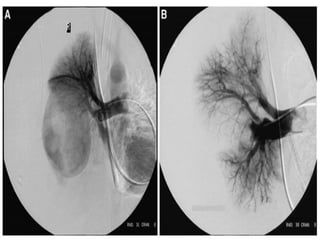

Indications

for

Recurrent

hemoptys

-is

Pre-

operati-

ve

Bronchial angiography

Massive

hemoptysis

Undiagnosed

(Sirajuddin and Lucien, 2008)